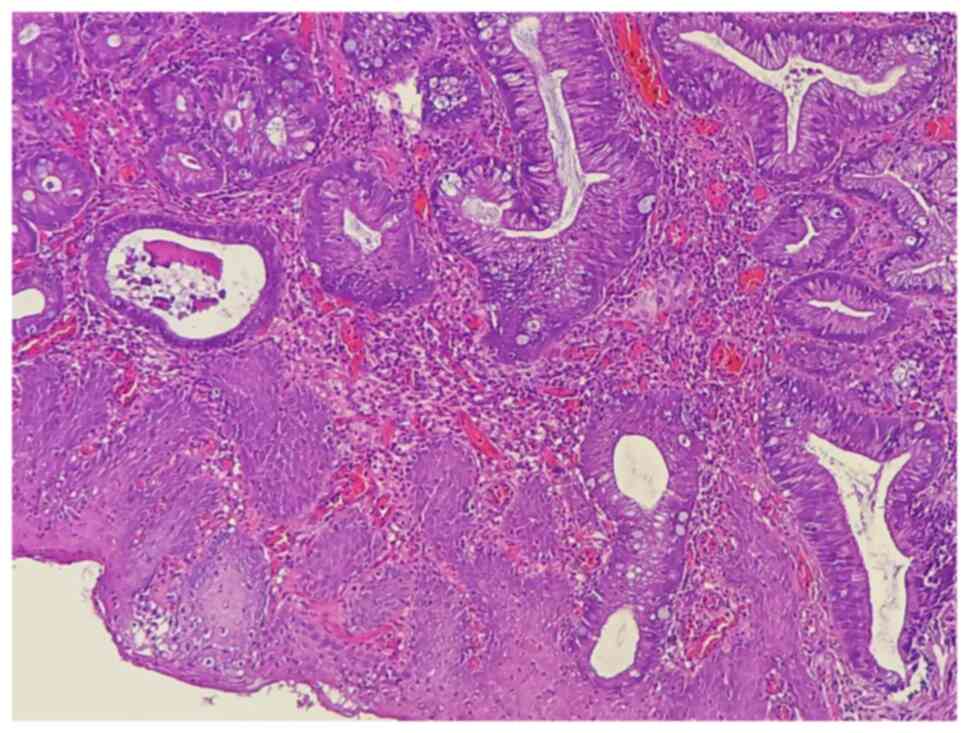

Clinical findings

The medical history of the patient included controlled diabetes mellitus, hypertension and multiple sessions of cystoscopic laser lithotripsy, as well as open vesical stone extractions. She had previously undergone a cystoscopy-directed TURBT to remove a mass from the urinary bladder, and a histopathological examination of the biopsy (performed at Rzgary Oncology Laboratory), identified the tumor as a moderately differentiated T2 adenocarcinoma (Fig. 1). Following this, the patient was referred to the Smart Health Tower (Sulaymaniyah, Iraq) for further management.

Figure 1

The stained section indicates numerous fragments of bladder tissue heavily involved by moderately differentiated adenocarcinoma.